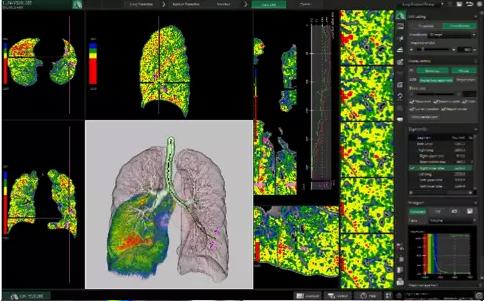

View X-Ray CT & MRI Scans Fast and Easily

Designed for surgeons, Pro Surgical 3D makes it easy to view patient scans quickly. Pro Surgical 3D facilitates the optimal 3D treatment and assessment workflows based on X-ray CT and MRI scans – and best of all, it’s FREE!

High-quality and fast 3D reconstruction and 3D rendering

Performs 3D reconstruction and volume rendering.

Window/level (brightness and contrast) presets.